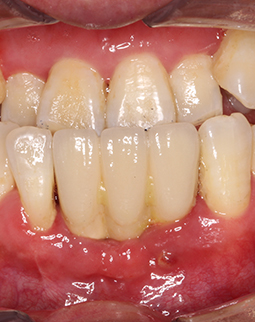

种牙之前我跑了很多医院,最终还是满意这里的种牙方案。说起缺牙,我和一般人还不太一样,我的门牙早些年因为摩托车车祸掉了三颗,和不少纠结“种植牙好还是镶牙好”的人一样,一开始我也因为镶牙便宜,选择了烤瓷牙联桥,几年过去了,发现这个烤瓷牙越来越难用了,一开始吃东西没有异常,这几年老是口臭,而且有金属黑线了,特别影响美观,跟人说话都好像没刷干净牙,我给你们看一下我种牙之前的口内照,有点恶心,请做好心理准备。

值得一提的是,我种牙之前把周围的炎症都提前处理了,做了深层的刮治和洁牙,把牙龈袋和牙缝的结石刮干净,还局部上了些消炎药。你们看下我的牙齿具体情况,黄色的都是牙结石,算严重了,牙龈也有些红肿对不对?很大一部分原因是因为那个烤瓷牙联桥导致的。